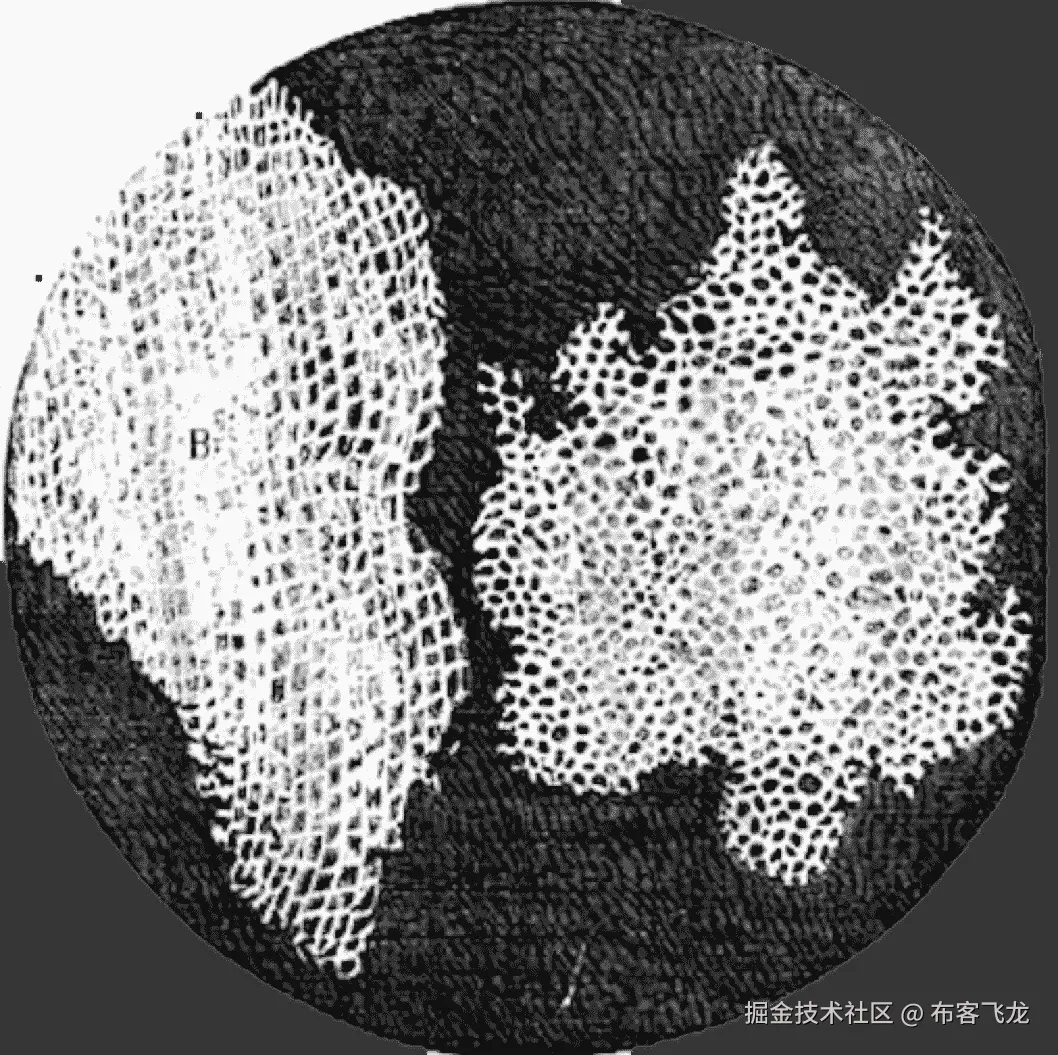

例如,参见下面的地图(基于这篇论文)。它基于对超过 200 万篇论文的分析显示了医学科学子领域之间的关系。研究人员和资助者可以使用这些地图在浩瀚的科学海洋中导航,并识别潜在的有趣论文和领域之间的联系。

来源:斯库平、比伯斯丁和伯尔纳(2013 年)